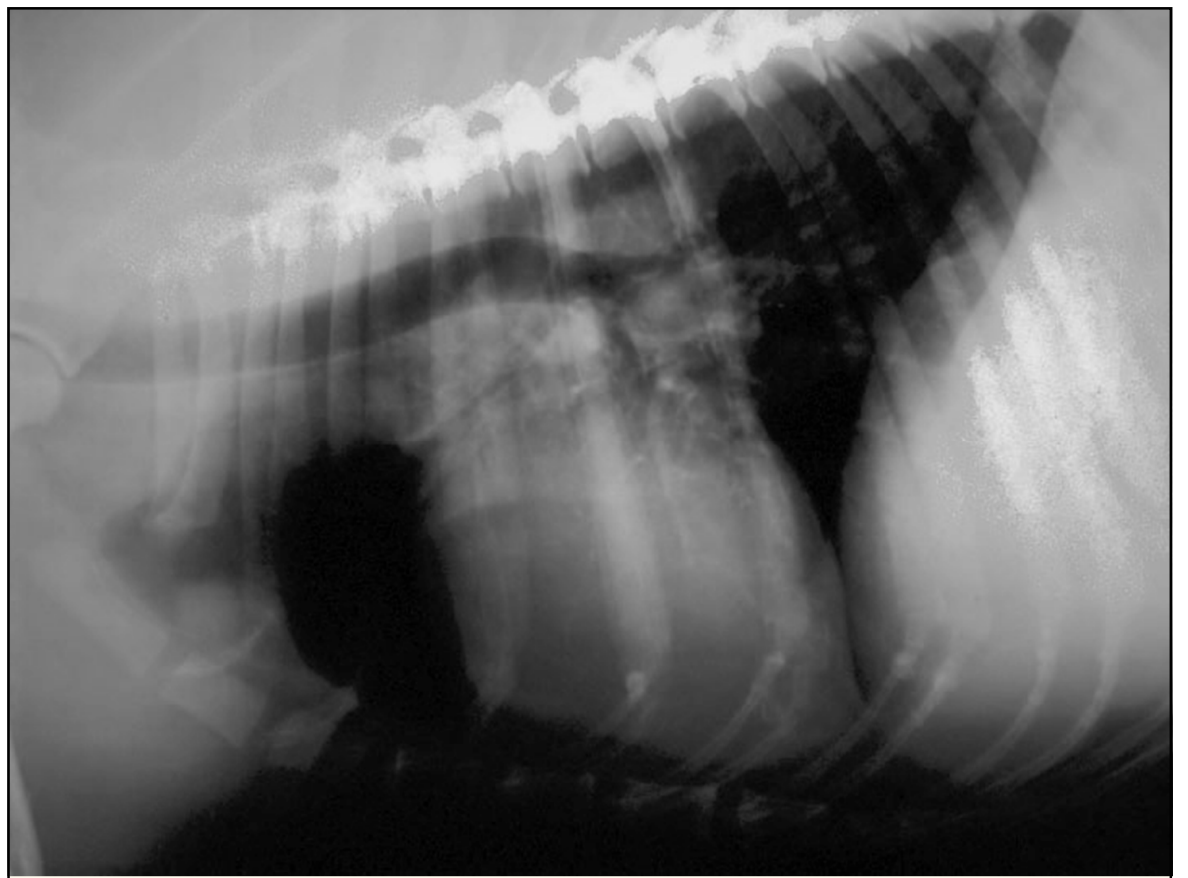

term image

st density over it, lung pinged up

gfluid filled